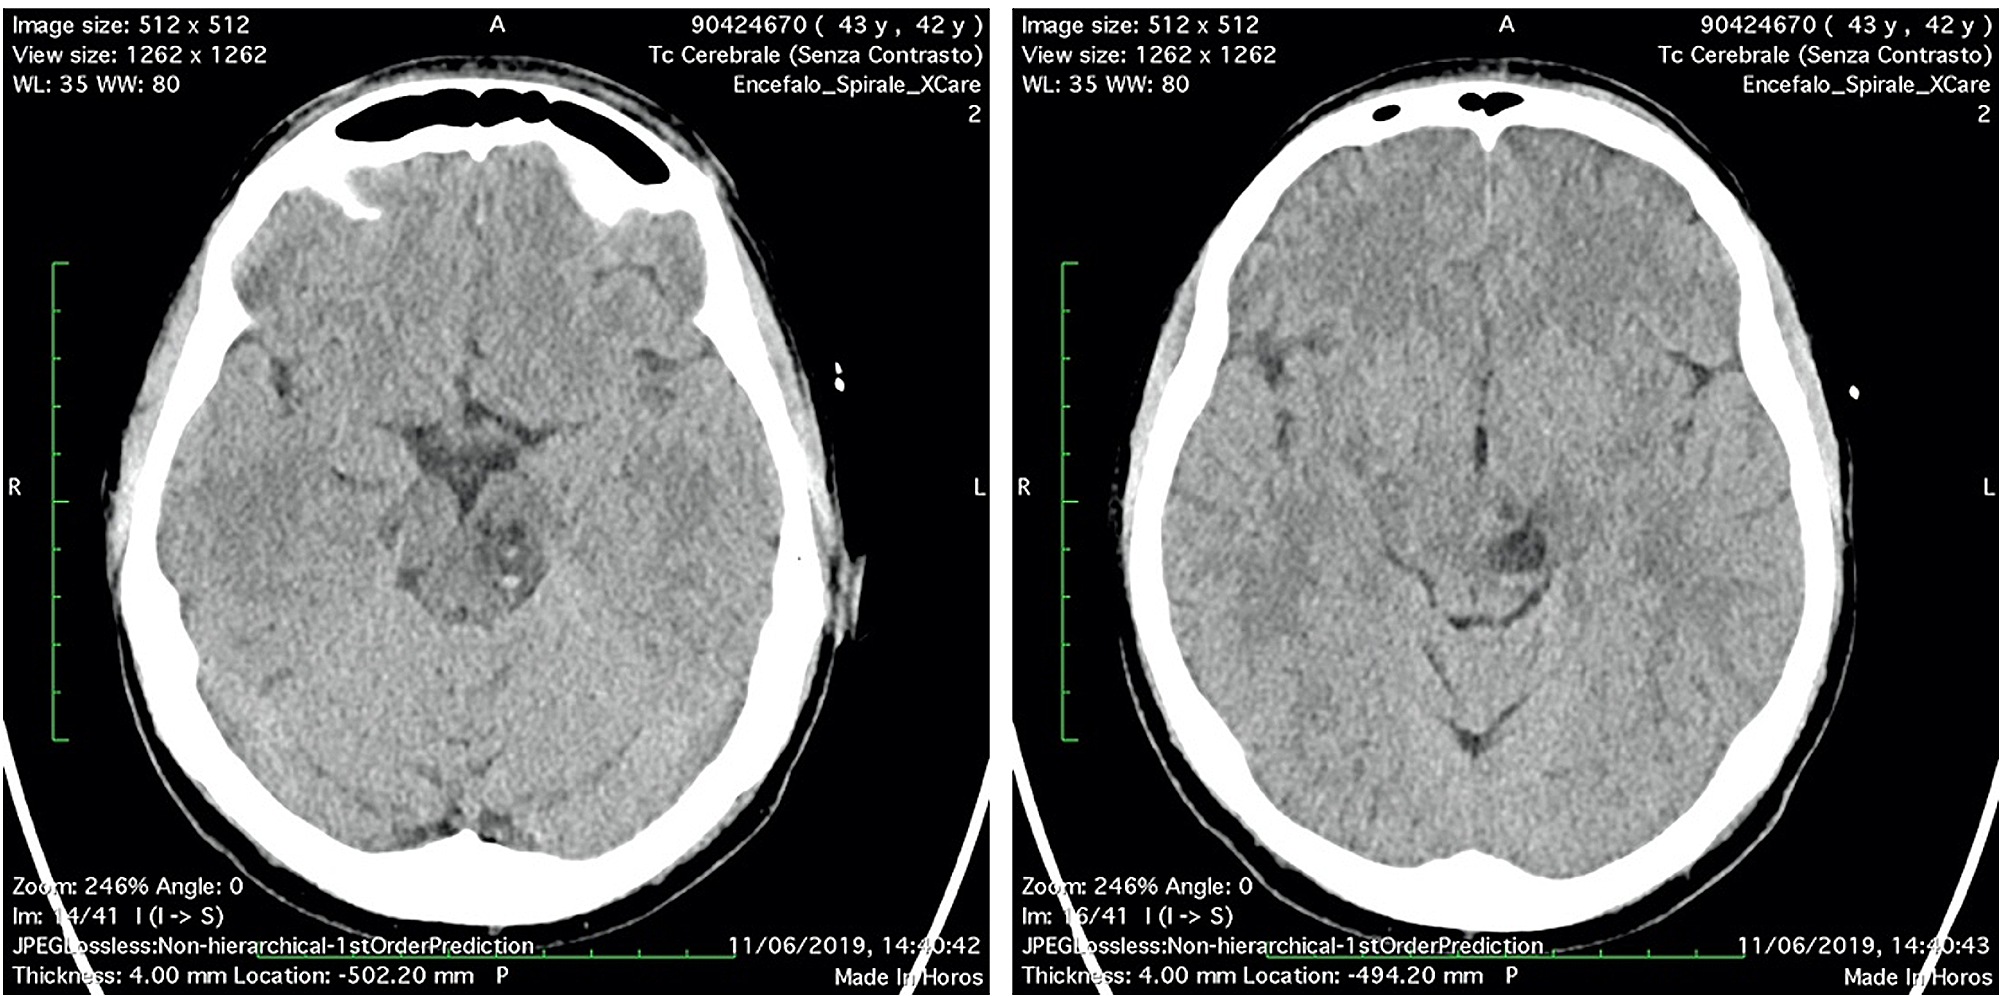

Two days after the surgery, diplopia and nausea were disappeared, vertigo persisted. The patient stayed six days more in hospital to follow the reconstruction of the scalp and to recover. Unfortunately, the patient had a reject of transplanted skin with necrosis and had to schedule a new surgery in a month later. Before discharge, a CT scan was performed in order to assess the midbrain lesion (Figure 4).

The patient was discharged and she continued the treatment for the scalp lesion and gradually recovered from vertigo. She repeated CT and MRI exams to follow the midbrain lesion up: a CT scan after one month (Figure 5) and a MRI scan after four months (Figure 6). A significant volume reduction of the midbrain lesion was observed.